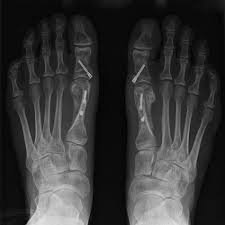

Die Chevron Osteotomie ist eine sehr effektive OP.

Während man beim Hallux valgus früher oft erst operiert hat wenn gar nichts mehr geht wird heute eher dafür plädiert zu operieren wenn der Schaden noch nicht zu komplexen Funktionsschäden im Bereich des Fußes geführt hat. Dabei muss es einen medizinischen Grund für die Operation geben. Zwei betroffene Frauen erzählen. Die Chevron Osteotomie ist eine sehr effektive OP. Die Ursachen liegen oft in der Kindheit. Im fortgeschrittenen Stadium ist nur noch ein operativer Eingriff möglich. Die Vielzahl von Behand. Meist schwillt diese Partie an. Ein Eingriff am Großzehenknochen meist eine Knochenumstellung Osteotomie begradigt die Zehe.